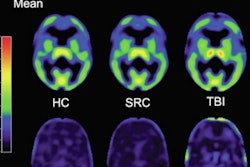

Researchers from Imperial College London performed PET and MRI in nine people with an average age of 44 who had a single moderate-to-severe traumatic brain injury. The brain injuries occurred between 11 months and up to 17 years before the start of the study. The participants were compared with 10 people with Alzheimer's disease and nine healthy participants.

PET was used to detect plaques in the brain, while diffusion-tensor MR imaging (DTI-MRI) visualized damage to brain cells that occurs after TBI.

Patients with brain injuries and those with Alzheimer's disease had plaques in the posterior cingulate cortex, which is affected early in Alzheimer's; however, only people with brain injuries had plaques in the cerebellum. The researchers also found increased plaque accumulation in patients with more damage to the brain's white matter.